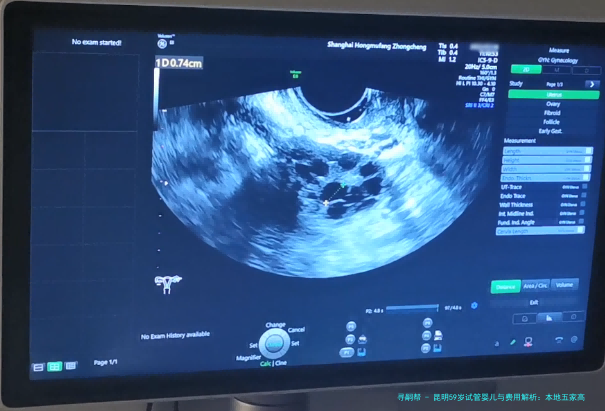

阴道B超监测排卵15080110100/次